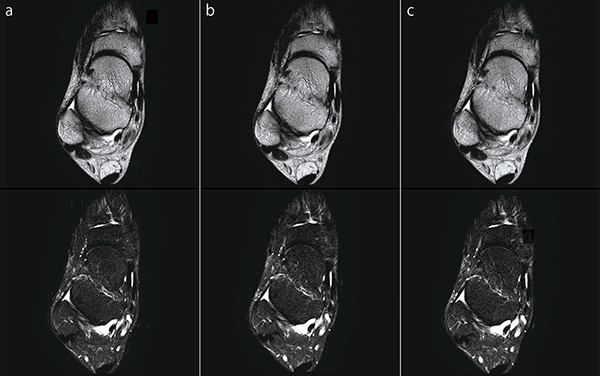

●足関節FatSep T2WI

図7 aは,IP-RAPIDを使用していない画像です。それに対して図7 b,cは,IP-RAPIDを使用しています。RAPID(IP-Recon)強度の選択によって画像のSNRと空間分解能の調整を行うことは,部位にかかわらず同様です。

図7 足関節FatSep T2WI(上段:in Phase画像,下段:脂肪抑制画像)

a:IP-RAPID off, Phase=1.5, Freq/Phase=320×288, scan time=2:55

b:IP-RAPID on, Phase=2.0, IP-Recon=Light, Freq/Phase=320×288, scan time=2:12

c:IP-RAPID on, Phase=2.7, IP-Recon=Medium, Freq/Phase=320×288, scan time=1:35

●膝関節PDWI

図10 aは,IP-RAPIDを使用していない画像です。それに対して図10 b,cはIP-RAPIDを使用して,撮像時間を維持したまま空間分解能を向上しています。頭部MRAと同様に,空間分解能を向上させるためにはFreq/Phaseを大きくする必要があります。そしてIP-RAPIDを活用することで,その結果生じる撮像時間の延長やSNR低下の影響を低減させることができます。

図10 膝関節PDWI

a:IP-RAPID off, Phase=1.6, Freq/Phase=288×288, scan time=2:58

b:IP-RAPID on, Phase=1.8, IP-Recon=Light, Freq/Phase=320×320, scan time=2:58

c:IP-RAPID on, Phase=2.0, IP-Recon=Medium, Freq/Phase=352×352, scan time=2:56